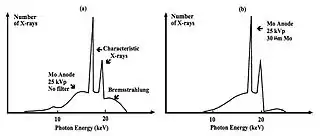

- Molybdenum (Mo) can be used instead of tungsten as the anode material in the X-ray tube (XRT). The Mo energy spectrum consists of K-Characteristic lines between 17 and 19 keV and a Bremsstrahlung continuum - see Figure 7.22. The Bremsstrahlung can be attenuated using an added Mo filter which preferentially eliminates the low energy radiation, that would otherwise be completely absorbed by the tissues and contribute little to image formation, as well as higher energy X-rays which would otherwise degrade subject contrast. This is an example of the application of K-edge filtration.